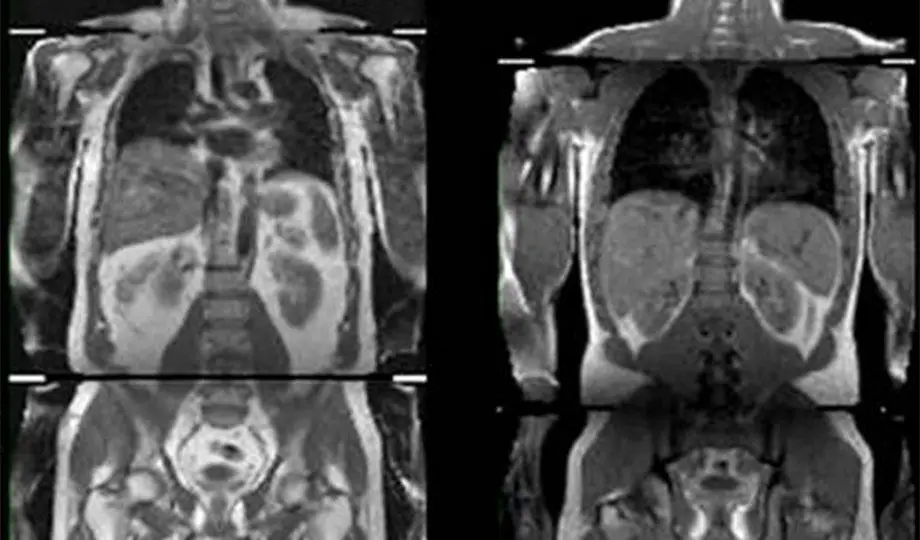

The team looked at data from the UK bio bank from more than 500,000 people aged between 37 and 73. They used MRI (magnetic resonance imaging) scans of these people’s waists to match where they stored extra fat with whether they showed signs of Type 2 diabetes, heart attack and risk of stroke.

(Image: CC by ImagingFat)